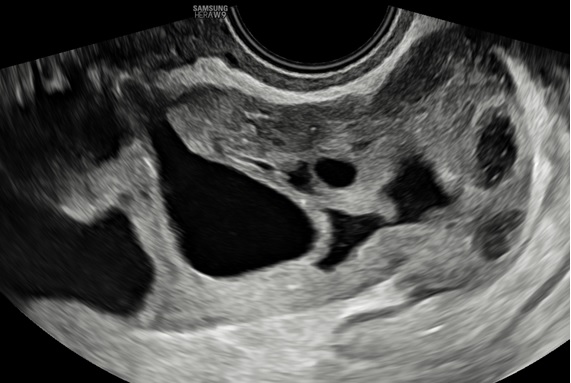

– Siêu âm: Tử cung và 2 buồng trứng bình thường. Ở cùng đồ sau có cấu trúc echo kém không đồng nhất dạng hình ống, có vách ngăn dày thông nhau, kích thước # 84x 89x 37 mm, bờ trong thành u không trơn láng, bên trong có nhiều mảng echo kém dạng mô đặc, tăng sinh mạch máu mức độ 2. Bụng và cùng đồ: không dịch.

– Chẩn đoán siêu âm: Huyết tụ thành nang. Chẩn đoán khác: áp xe phần phụ.

Hình 5: Siêu âm ngã âm đạo cho thấy thành u có tăng sinh mạch máu độ 2